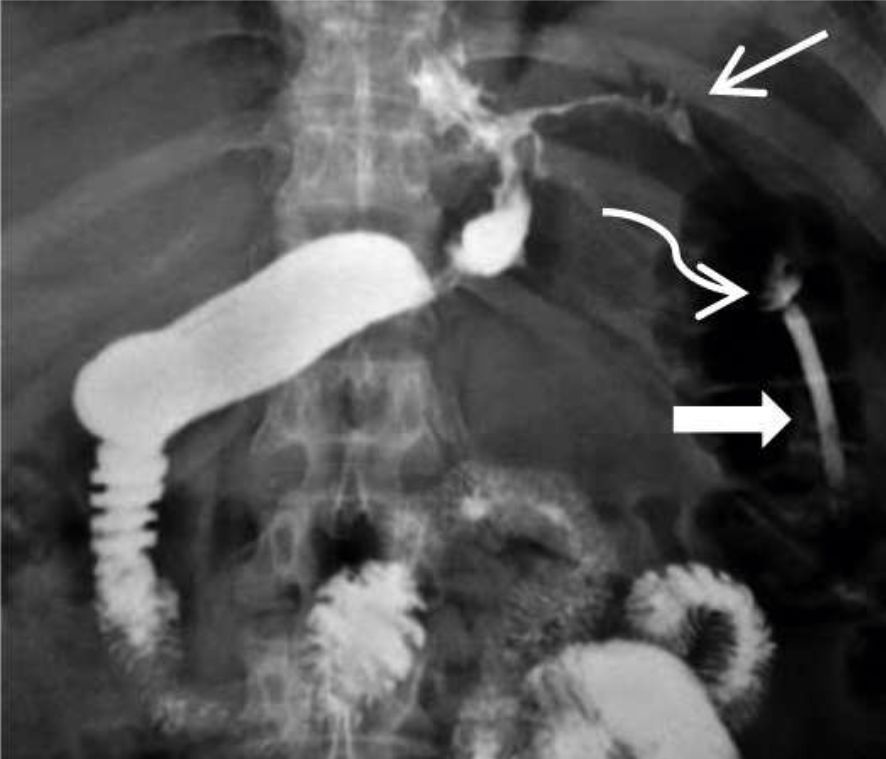

Figura 4

EGD en proyección AP

donde se observa trayecto fistuloso filiforme superior izquierdo (flecha fina) con pequeña colección en su sector distal (flecha curva) y catéter de drenaje laparoscópico (flecha gruesa). (Paciente Nº 14)

La principal utilidad del estudio de EGD post-operatorio es el seguimiento evolutivo de las fugas drenadas hasta su cierre. Figuras 4,5 y 6.